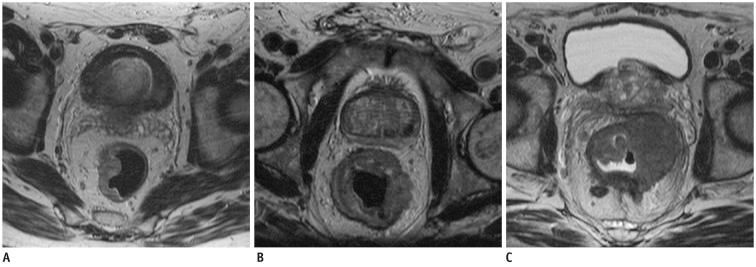

Seventy-three patients with primary rectal cancer underwent high-resolution MRI with a phased-array coil performed using 60-80 mL room air rectal distention, 1-3 weeks before surgery. MRI results were compared to postoperative histopathological findings. The overall MRI T staging accuracy was calculated. CRM involvement prediction and the N staging, the accuracy, sensitivity, specificity, positive predictive value (PPV) and negative predictive value (NPV) were assessed for each T stage. The agreement between MRI and histological results was assessed using weighted-kappa statistics.

The overall MRI accuracy for T staging was 93.6% (k = 0.85). The accuracy, sensitivity, specificity, PPV and NPV for each T stage were as follows: 91.8%, 86.2%, 95.5%, 92.6% and 91.3% for the group ≤ T2; 90.4%, 94.6%, 86.1%, 87.5% and 94% for T3; 98,6%, 85.7%, 100%, 100% and 98.5% for T4, respectively. The predictive CRM accuracy was 94.5% (k = 0.86); the sensitivity, specificity, PPV and NPV were 89.5%, 96.3%, 89.5%, and 96.3% respectively. The N staging accuracy was 68.49% (k = 0.4).

MRI performed with rectal lumen distention has proved to be an effective technique both for rectal cancer staging and involved CRM predicting.